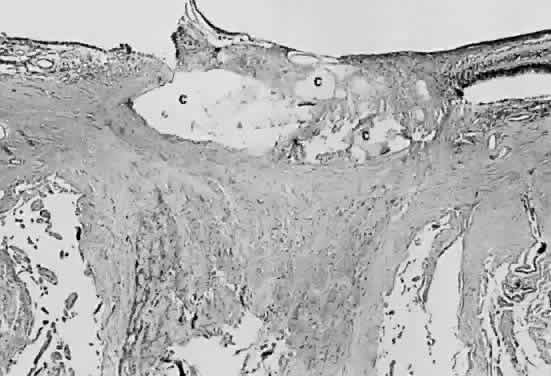

Fig. 19. Histologic section demonstrating response of the pigment epithelium to injury. The sclera is at the bottom the micrograph; the choroid (c) contains scattered red blood cells and is edematous. The vitreous (v) also contains hemorrhage. Locate the pigment epithelium (short arrows) at the left third of the micrograph and notice the ribbons of pigment epithelium that proliferate into the membrane, partially formed by fibrous tissue (F). Bone (long arrow) also is present and probably was deposited by metaplastic pigment epithelium.

Black changes in the fundus usually are the result of changes occurring in the retinal pigment epithelium, which is capable of a variety of responses to injury. It may lose pigment, enlarge and gain pigment (hypertrophy), or replicate (hyperplasia). It also may undergo change to another type of adult tissue such as fibrous tissue or bone (metaplasia) (see Fig. 19).

When the pigment epithelium responds by hyperplasia, it deposits basement membrane and frequently deposits collagen (metaplasia). Thus, pigment epithelial hyperplasia, often accompanied by metaplasia, may result in a lesion that is mildly elevated. The bone that appears in phthisical globes is presumed to be derived from metaplastic pigmented epithelium.